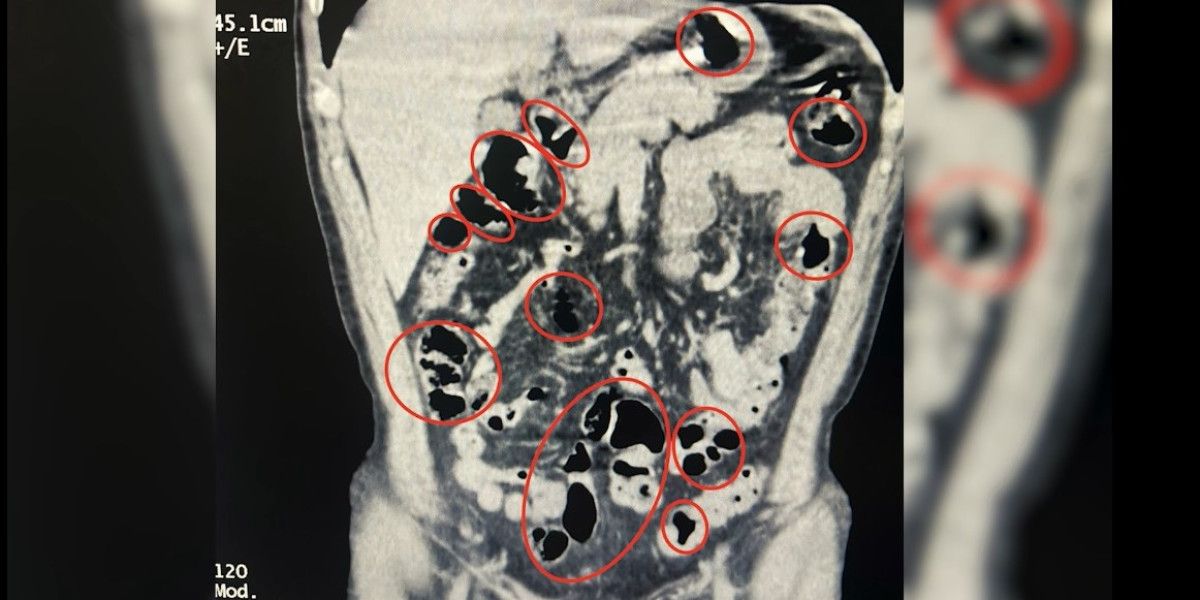

Tatvan Devlet Hastanesi’ne götürülen şüphelilerin burada yapılan röntgen ve tomografi incelemelerinde de mide ve bağırsaklarında yabancı cisimler tespit edildi.

Tıbbi müdahale sonucu şüphelilerin yuttuğu 14 kapsül çıkarıldı.